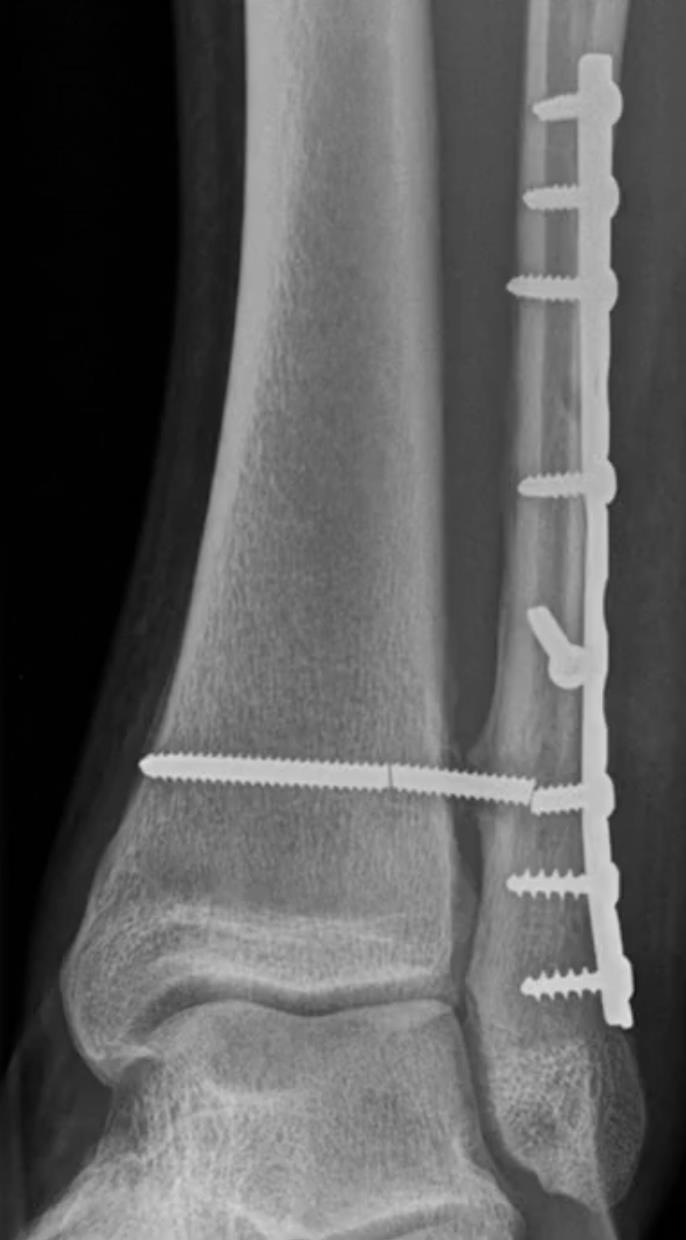

Syndesmosis TightRope® XP Implant System

• Design

• The Syndesmosis TightRope XP implant system features a unique delivery mechanism that allows the user to insert a Syndesmosis TightRope implant without pulling a needle through the medial skin

• Gives the user control to flip the medial oblong button below the skin for less soft-tissue interposition

• Trocar Style Drill Bit

• Reduces skiving off the fibula when drilling in the transmalleolar plane 30˚ anterior to the coronal plane

• Indications

• Provide fixation during the healing process following a syndesmotic trauma

• Fixation of syndesmosis (syndesmosis disruptions) in connection with Weber B and C ankle fracture

• The syndesmosis should be formally reduced prior to fixation and confirmed using fluoroscopy, direct visualization during open reduction, or both based on surgeon preference and severity of injury